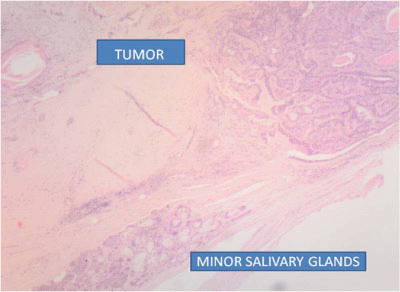

Final diagnosis: Cytopathologic study revealed a minor salivary gland tumor, with biphasic pattern and low prolipheration index with well defined borders and surrounded by a thick layer of fibrous tissue. Ki-67 prolipheration index <2%. Cytokeratin AE1/AE-3 was positive in the cellular areas and carcinoembryonic antigen (CEA) was negative demonstrating a PA with predominant cellular component (Figure 4). In this case multiple dilated thin-walled blood vessels filled with intraluminal deposits of eosin positive material were found leading to an intraoperative diagnosis of malignancy (Figure 5).

Figure 4 Microphotograph of a tumor showing a mixture of epithelial, myoepithelial and stromal components with normal minor salivary glands and a thick layer of fibrous tissue typical of minor salivary glands Pleomorphic Adenoma. Hematoxylin/eosin staining.